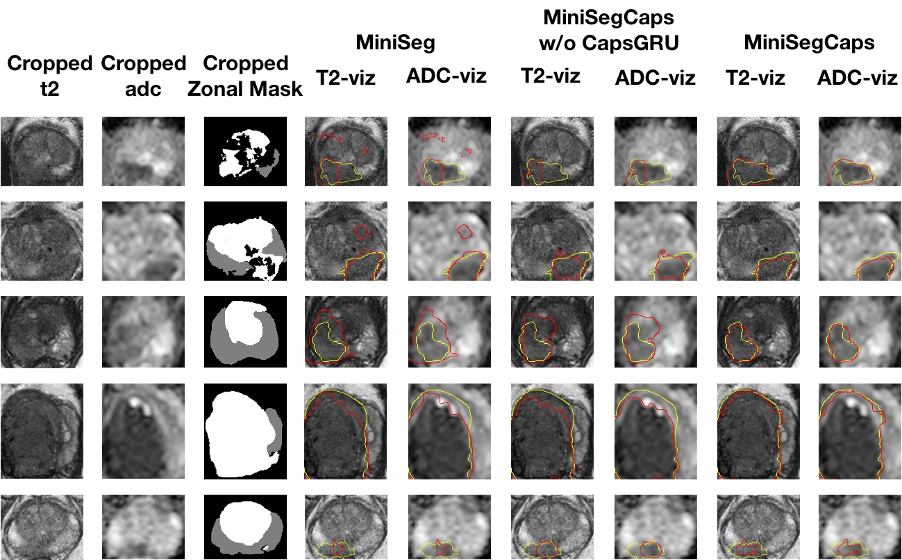

Fig.3 illustrates a visual comparison of the cropped T2, cropped ADC, cropped zonal mask, lesion ground truth, and predicted lesion mask by MiniSegCaps on T2 and ADC images. Our model successfully produced satisfactory segmentation of prostate cancer and revealed the spatial relationship between the zonal mask, lesion on T2, and ADC, which might help lesion location and classification. We also obtained consistent segmentations across adjacent slices within one volume, as shown in Fig.4. Our MiniSegCaps obtained better results than MiniSegCaps w/o CapsGRU, which indicates that CapsGRU captured the spatial information across adjacent slices as expected, boosting the prostate cancer segmentation performance. Moreover, our model achieved acceptable performance on BPH segmentation as shown in Fig.6.

Fig. 3. Visualization of lesion segmentation results among different cases. The yellow contour is the ground truth, and the red contours are from the deep learning predictions.